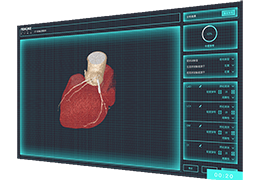

ANYTHINK 经导管主动脉瓣膜置换术分析系统